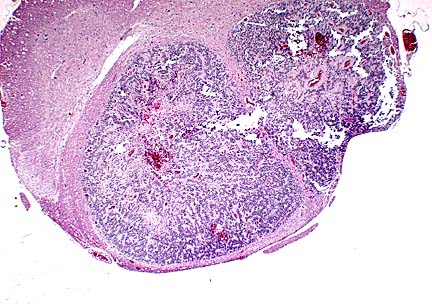

Case IV -96-1(AFIP 2548412)

Signalment: 55-week-old female Wistar rat.

Infiltrative neoplasm in the spinal cord of a Wistar rate. Note the compression and distortion of the central canal. (HE, 40X, 54K)

Infiltrating cords of ependymoma in the spinal cord of a Wistar rat. (HE, 100X, 115K)

Rosette formed around neuropil characteristic of ependymoma. (HE, 400X, 66K)

History: Rat was in an untreated group on an 104 week carcinogenicity study. The rat was sacrificed during the 48th week of the study due to lameness in both hind limbs.

Contributor's Diagnosis and Comments: Glioma, anaplastic.

This spinal cord neoplasm presented a diagnostic challenge for our pathology group. Use of this recently-introduced Wistar-derived strain for carcinogenicity studies has not been reported. References to spinal cord tumors in other rat strains are brief and infrequent, and the occurrence of spinal cord neoplasms is extremely rare in our extensive experience with Sprague-Dawley rats. The cells of this neoplasm are forming pseudorosettes and cords in some areas, however, the cells are quite pleomorphic, true rosette formation is not evident, and cell margins are often distinct. Depending on the section, the participant may see a single well-delineated mass, or two masses separated by a fibrous stroma that represent branching by the main tumor. Mitotic activity is very high, and clusters and cords of cells are often surrounded by an amorphous eosinophilic matrix. Common features of other central nervous system neoplasms, such as astrocytoma, oligodendroglioma, meningioma, ependymoma, and granular cell tumor were not evident. This neoplasm may represent an extremely anaplastic variant of a glial tumor, and as such, be difficult to categorize according to classical criteria. Cytochemical studies may be contributory, but were unavailable to us.

AFIP Diagnosis: Spinal cord: Ependymoma, Wistar rat, rodent.

Conference Note: The participants agreed with the contributor's comments on this difficult case. The Department of Neuropathology of the AFIP also reviewed the case. The histopathologic features are those of a neuroepithelial neoplasm with glial processes forming neuropil-prominent perivascular pseudorosettes. The differential diagnosis based on the H&E sections was ependymoma versus paraganglioma. The absence of immunohistochemical staining for synaptophysin supports ependymoma. Thus, we agree with the contributor that the neoplasm is in the glial group but favor the more specific diagnosis of ependymoma. Other immunohistochemical and histochemical stains were noncontributory. The hypercellularity, frequent mitoses, necrosis and vascular proliferation are indicators of aggressive behavior.

Ependymomas are rare neoplasms of neuroectodermal origin that develop from the ependymal lining of the ventricles of the brain and central canal of the spinal cord. They have been reported in rats, cats, dogs, non-human primates, cattle, horses, deer, and fish. Ependymomas are usually slow-growing and frequently cause extensive tissue damage by compressing the adjacent neuropil. Anaplastic varieties can infiltrate the brain or spinal cord and metastasize via the cerebrospinal fluid. Obstruction of the fourth ventricle can result in hydrocephalus.

Ultrastructurally, ependymal cells have intercellular tight junctions. Some may be ciliated and contain blepharoplasts. Blepharoplasts can sometimes be demonstrated with phosphotungstic acid hematoxylin (PTAH). Immunohistochemically, ependymomas are variably stained for vimentin, GFAP, and keratin.